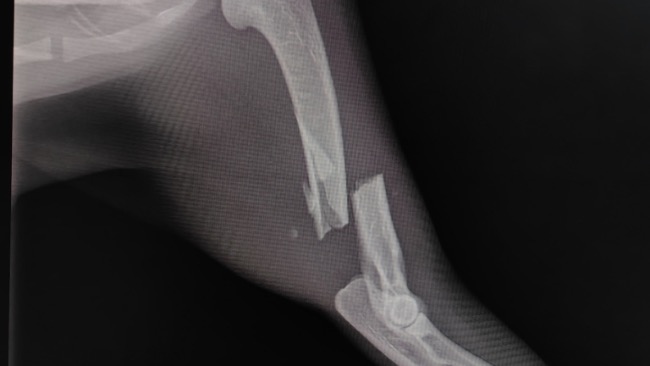

Zamiast chodzić – skakała. I już wiedziałyśmy, że to nie zwykła „dziwna maniera”. Diagnoza zmroziła nas: połamane dwie przednie łapki. Maleństwo nie może się poruszać, leży pod kroplówkami, wycieńczone, bez apetytu, w inwazji pcheł i wszołów… Sutki nabrzmiałe, z których leci mleko – a więc gdzieś tam czekały na nią kocięta, które nigdy nie dostaną swojej mamy z powrotem.